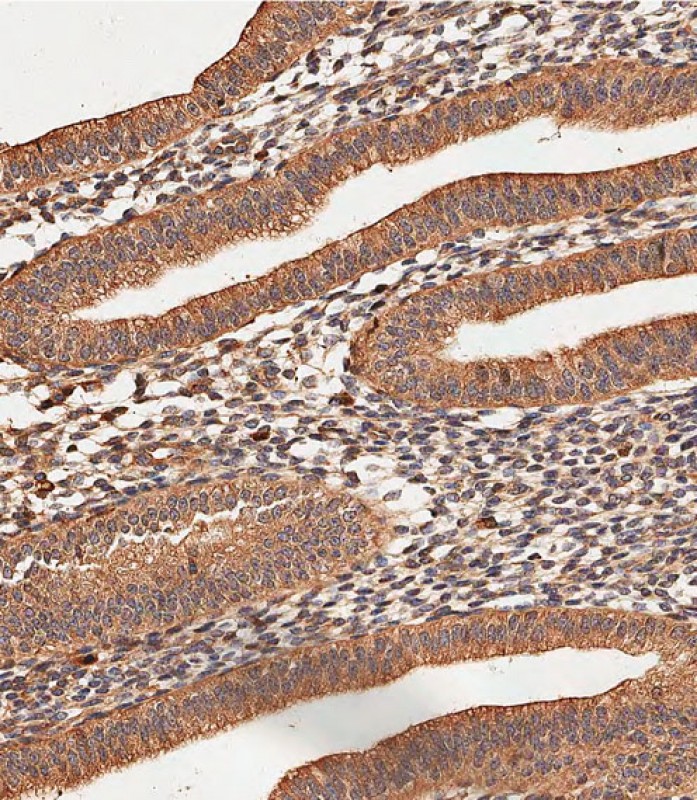

Immunohistochemical analysis of paraffin-embedded Human heart tissue using P34604 performed on the Leica® BOND RXm. Tissue was fixed with formaldehyde at room temperature, antigen retrieval was by heat mediation with a EDTA buffer (pH9. 0). Samples were incubated with primary antibody(1:500) for 1 hours at room temperature. A undiluted biotinylated CRF Anti-Polyvalent HRP Polymer antibody was used as the secondary antibody.

Immunohistochemical analysis of paraffin-embedded Human uterus tissue using P34604 performed on the Leica® BOND RXm. Tissue was fixed with formaldehyde at room temperature, antigen retrieval was by heat mediation with a EDTA buffer (pH9. 0). Samples were incubated with primary antibody(1:500) for 1 hours at room temperature. A undiluted biotinylated CRF Anti-Polyvalent HRP Polymer antibody was used as the secondary antibody.